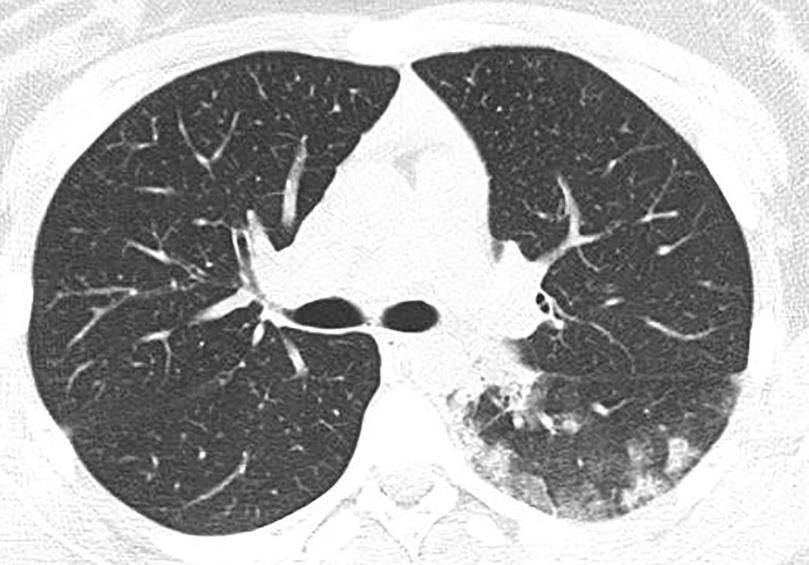

Acute Pediatric COVID-19: CT

21 Imaging of Covid 19 infection in children

3 Phases

Early: "Halo" sign

Local infection

Progressive: Diffuse GGO

Developed: Consolidation

Surr vasc congestion

Inflammation - adj alveoli

Alveoli fill with fluid/cells

CT

• Bilateral & multifocal GGO, +/Consolidations or both

• Halo sign

• Peripheral and subpleural

• Bronchovascular thickening